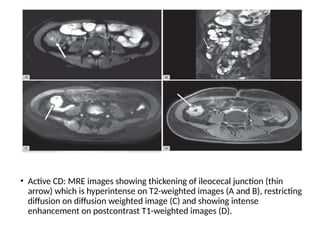

• Active CD: MRE images showing thickening of ileocecal junction (thin

arrow) which is hyperintense on T2-weighted images (A and B), restricting

diffusion on diffusion weighted image (C) and showing intense

enhancement on postcontrast T1-weighted images (D).

• Active CD:MRE images showing thickening of ileocecal junction (thin arrow) which is hyperintense on T2-weighted images (A and B), restricting diffusion on diffusion weighted image (C) and showing intense enhancement on postcontrast T1-weighted images (D).